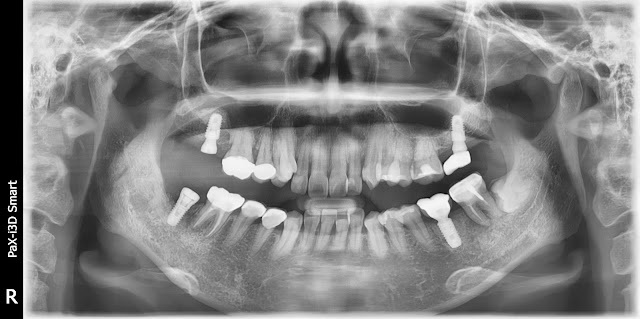

A 51-year-old male patient. Implant placement is planned for the maxillary tooth #26 area. Due to inadequate bone on the palatal root side, an extraction was performed with simultaneous socket preservation. Implant placement was performed after approximately 4 months of socket preservation. Here is a photo of the implant in place. Implants from Ossteo Bionics, specifically the SB implants, were placed during the procedure. The implant was placed using a crestal approach in the maxillary area, and BioCrea was used for grafting during implant placement. This is a post-operative radiograph after the surgery. The bone density at the time of implant placement was approximately D3. Here is a brief summary of the implant surgery record I use: I always make sure to record the bone quality, initial stability, and generally, I note down the expected prosthetic placement date at the time of implant placement. Here is a photo taken about 3 months after implant placement. While I don't always m...